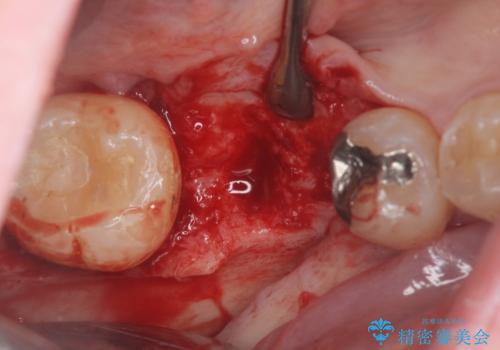

保存不可能な虫歯、インプラントによる機能回復

- 長年放置した虫歯痛み、治療を希望され来院されました。

右下の大臼歯は、虫歯が重度に進行し保存が不可能な状況です。

抜歯後、骨の吸収を造成にて回復しインプラント治療を進めます。